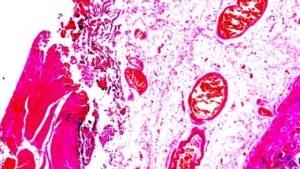

При раке на очень ранней стадии (T1a) некоторые врачи могут порекомендовать нехирургическое лечение, называемое эндоскопической резекцией слизистой оболочки. При начальных стадиях (стадии 0 или I), когда рак еще находится только в желудке, хирургическое вмешательство используется для иссечения части желудка, содержащей рак, и соседних лимфоузлов. Это называется субтотальной или частичной гастрэктомией. При частичной гастрэктомии хирург сшивает небольшую часть желудка с пищеводом или тонким кишечником.